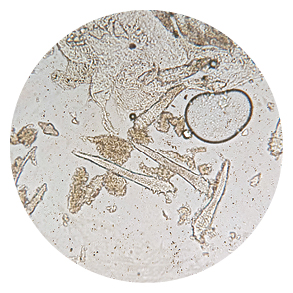

根據研究,玫瑰斑患者皮膚中的蠕形蟎蟲數量一般人來得多,當季節交替而使溫差變化較大,蠕形蟎蟲也會變得特別活躍。葉家銘醫師說明,蠕形蟎蟲是一種皮膚寄生蟲,其實每個人臉上都有,在免疫系統正常的前提下,並不會使人感覺不舒服。然而,如果患者長期感覺疲憊、免疫力下降,或使用了不適合的藥物,就可能破壞身體的免疫平衡,讓蠕形蟎蟲的數量過度增加。

一般來說,皮膚科醫師會先從外觀診斷,再用顯微鏡檢查,若發現蠕形蟎蟲確實異常增加,通常會優先選用「雙效殺蟎蟲乳膏」來改善。葉家銘醫師表示,雙效殺蟎蟲乳膏是一種含有伊維菌素成份(Ivermectin)的藥物,可以殺死蟎蟲、抑制發炎物質,抑制丘疹及膿皰的產生,其標準用量是每次1公克(約兩個指節長度),初期會建議先以「漸進增量」的方式塗抹,若沒有明顯不適,再提升到標準用量。如此持續1~3個月,就能看見明顯的改善,3~6個月之後膚況會更加穩定。